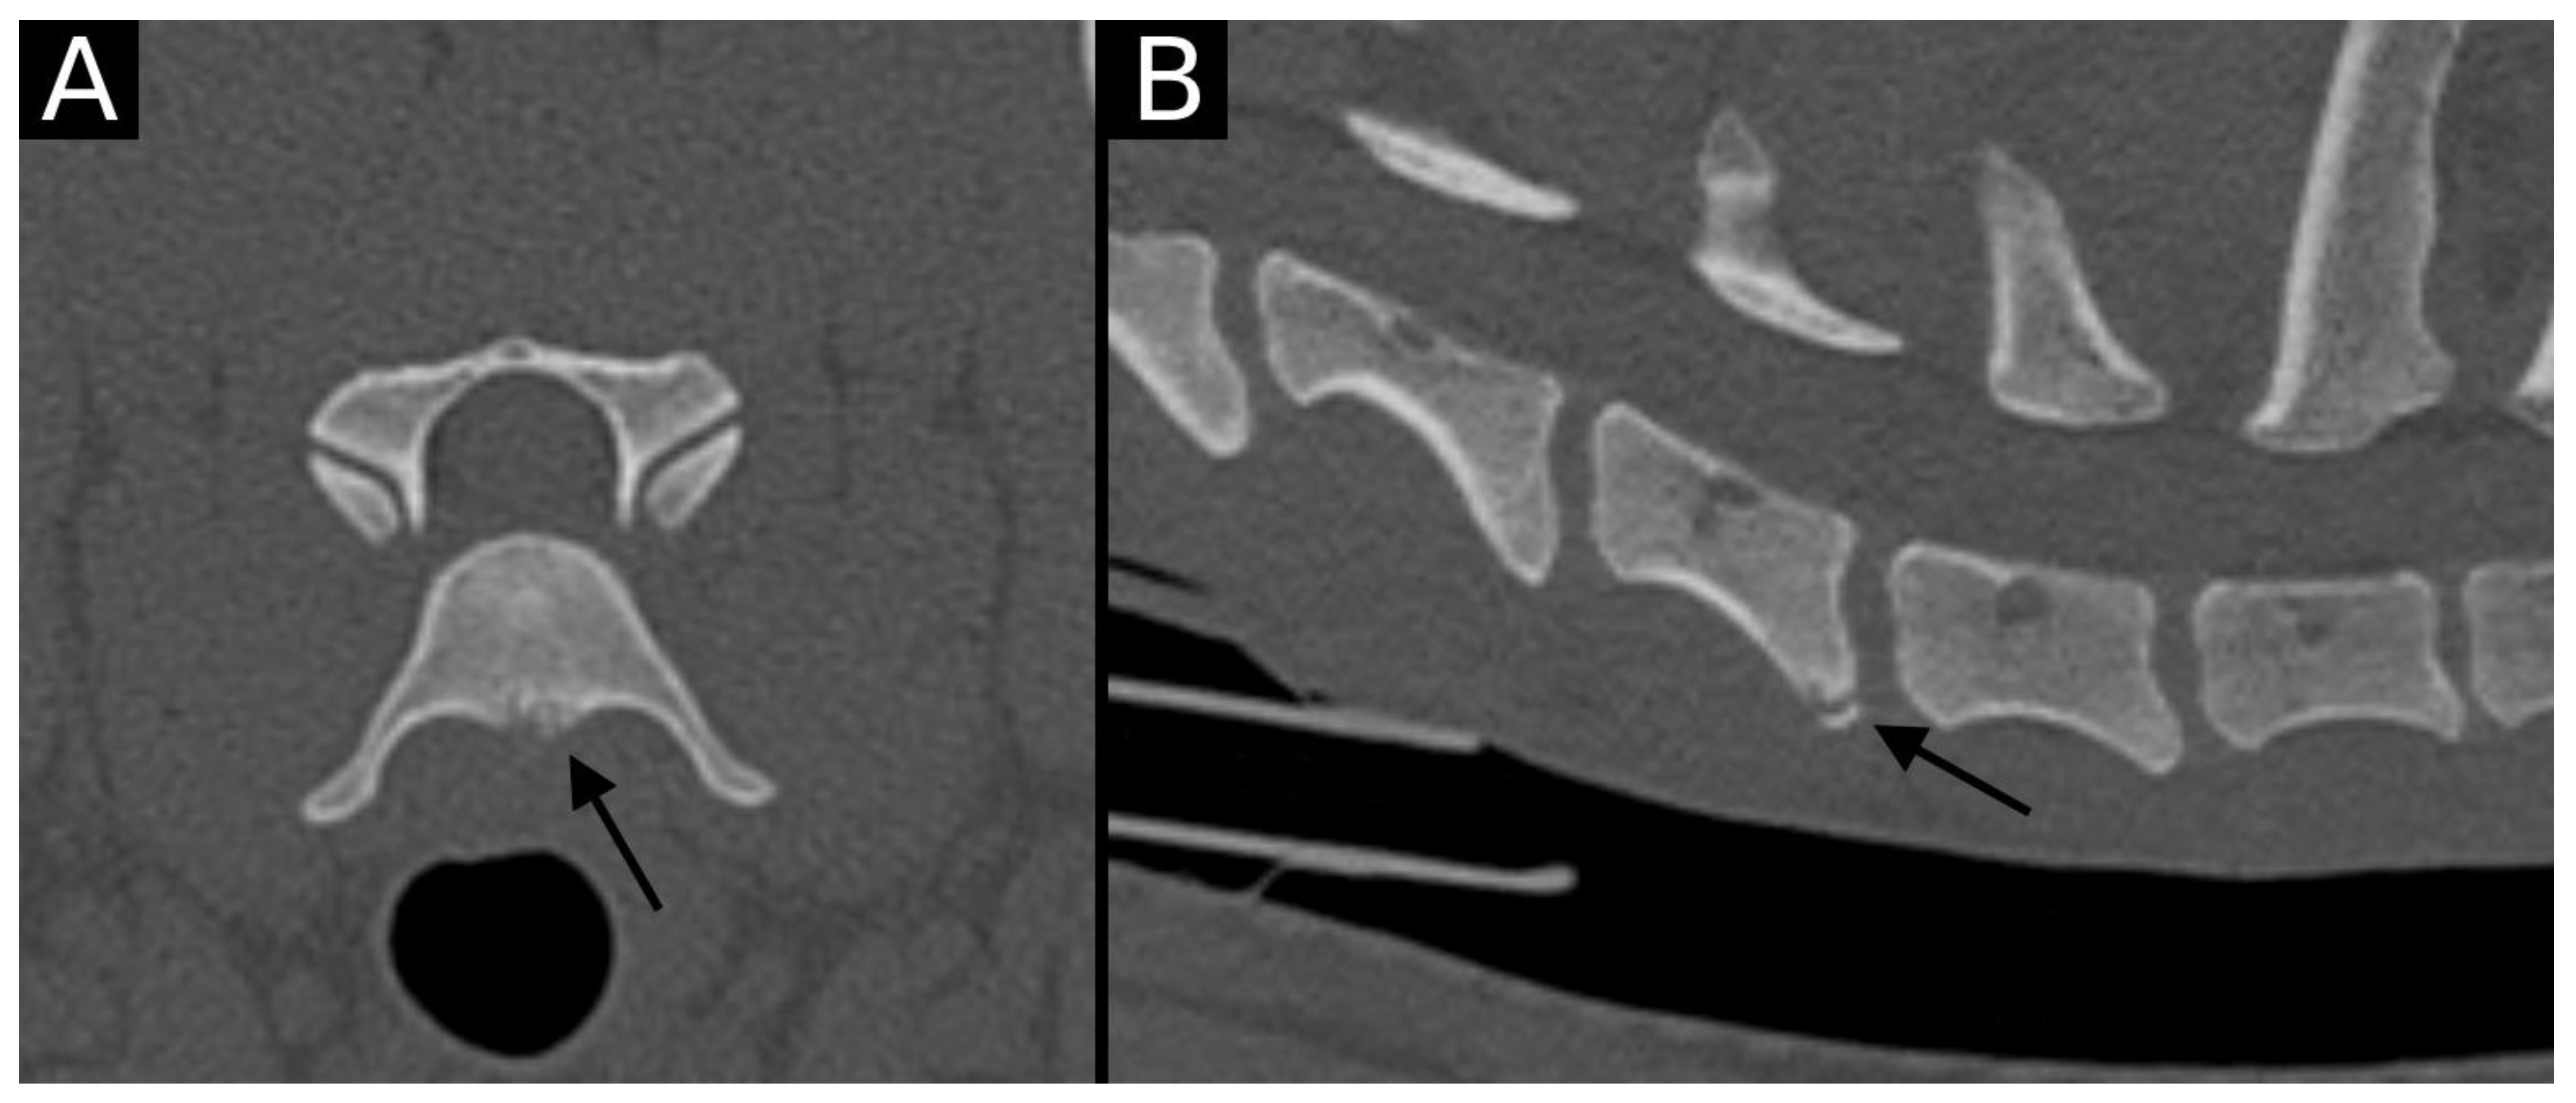

The junction between the endplates and intervertebral discs of the cervicothoracic junction (C6–C7, C7–T1 and T1–T2) were evaluated for the presence of alterations. When present, they were also graded and scored for EPJA, IVD herniation, spondylosis deformans, endplate sclerosis, articular process joint osteoarthrosis, and the presence of vertebral morphological abnormalities. The scoring system for endplate junction alterations and other spinal abnormalities was based on the proposed scoring by Tellegen et al. [13] for presumed EPJF at the lumbosacral spine. Endplate junction alterations were classified into four types (A, B, C, D): Type A involved presence of irregularity of the endplate margins without an obvious free fragment (Figure 1 and Figure 2); Type B involved avulsion evidenced by a thin rim of bone associated with a defect in the dorsal edge of the adjacent endplate (Figure 3); Type C included frank avulsion of a bony fragment (Figure 4) and Type D included presence of bony avulsion of both endplates. If EPJA was present, location (dorsal or ventral) and lateralization of the defect were also recorded. IVD herniation was graded from grades 0 to 3: grade 0 indicated no to mild (0–24%) herniation; grade 1 indicated mild to moderate (25–49%) herniation; grade 2 indicated moderate to marked (50–74%) herniation; grade 3 indicated marked herniation to complete obliteration (75–100%) of the vertebral canal by disc material. Spondylosis deformans was scored from grades 0 to 3: grade 0 indicated no enthesophytes; grade 1 indicated a small enthesophyte at the edge of the epiphysis that does not extend past the endplate; grade 2 indicated the presence of an enthesophyte that extends beyond the endplate but does not connect to the adjacent vertebra; and grade 3 indicated connecting enthesophytes from adjacent vertebrae forming a mineralized bridge. The other mentioned abnormalities (IVD mineralization, endplate sclerosis and articular process joint osteoarthrosis) were scored as present (1) or absent (0).

Figure 4. Transverse (A) and sagittal (B) reconstructions in bone algorithm. The ventral aspect of the caudal endplate of C6 has a well-defined, mildly irregular contour defect lined by mild sclerosis. A well-defined bone fragment (arrow) is observed mildly ventrally displaced with respect to the endplate. This is compatible with EPJA Type C.